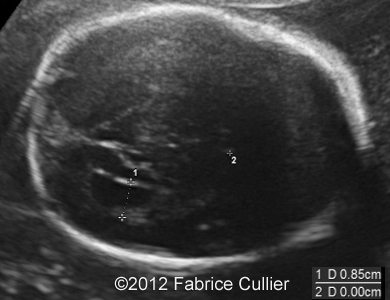

Images 1, 2: A transversal plane of the skull, too round (Brachycephaly).

1A

1B